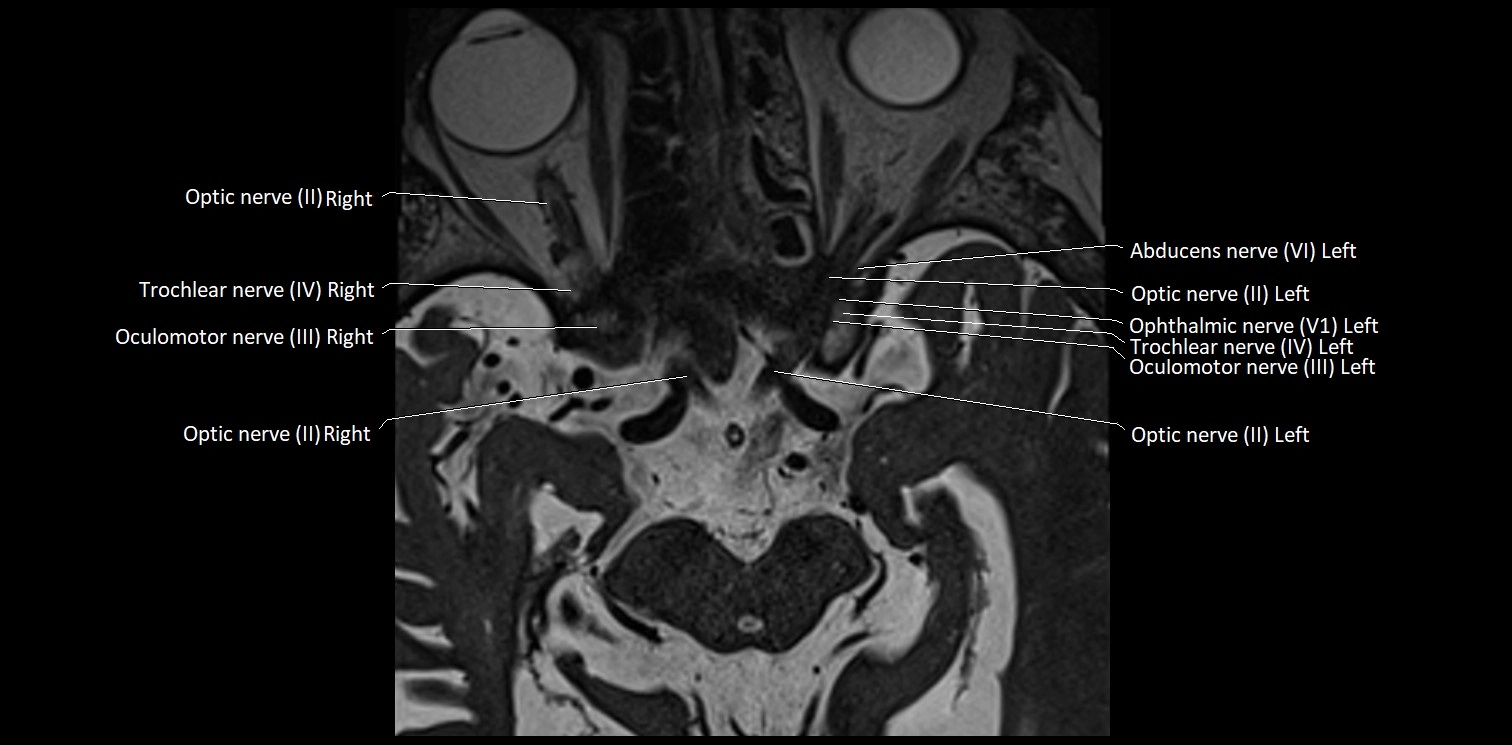

MRI images

image